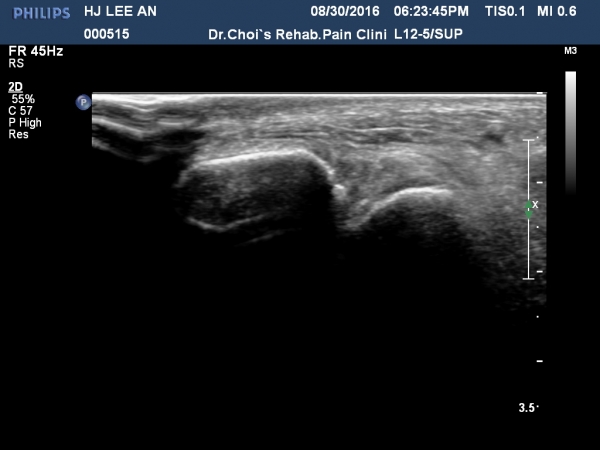

¸»´Ü ¾ÕÂʰæ°ñºñ°ñÀδë(distal anterior tibiofibular ligament) Á¾´Ü¸é°Ë»ç¿¡¼­ ƯÀÌ ¼Ò°ß º¸ÀÌÁö ¾ÊÀ½(»çÁø 3).